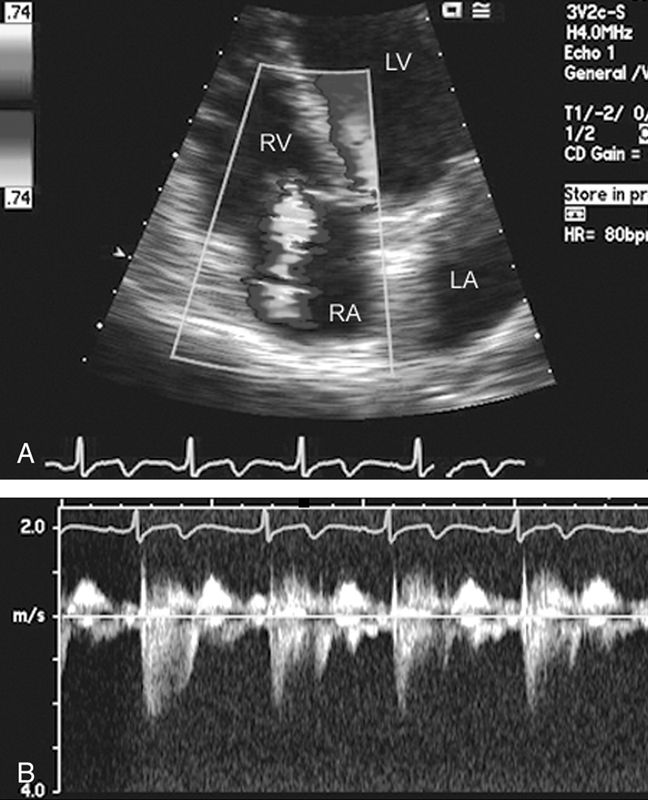

فحوصات تشخيصية لبعض امراض القلب والشرايين التاجية